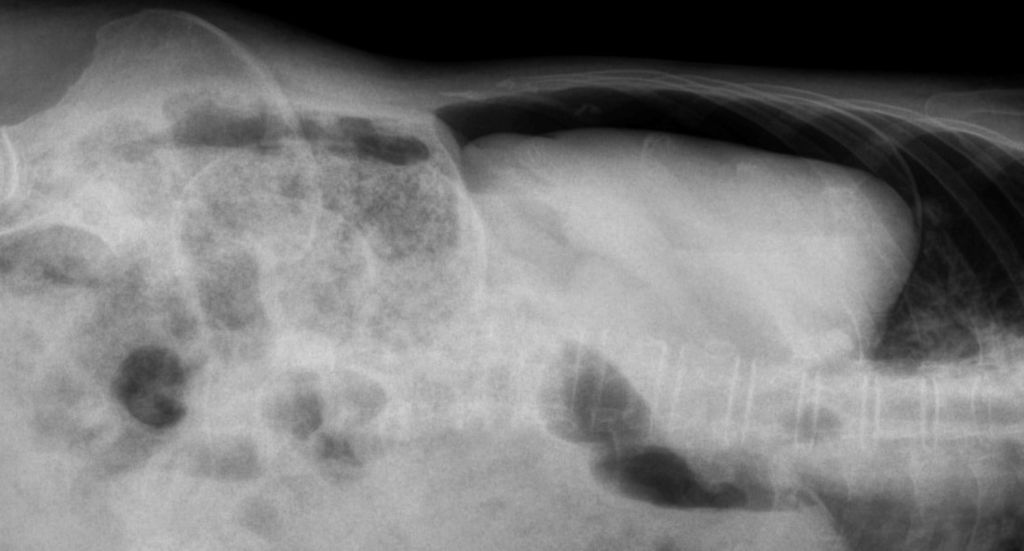

La radiographie, irremplaçable dans certaines pratiques vétérinaires.